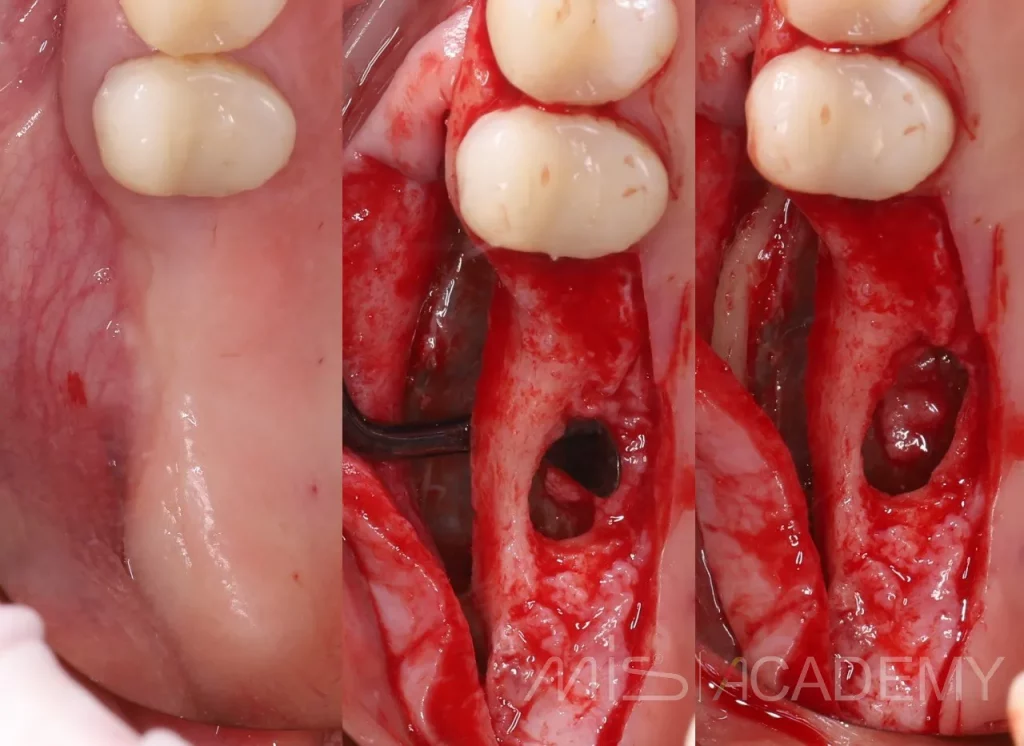

У пациентки в анамнезе удаление 26-28 и соустье с ВЧП, костный дефект дна пазухи.

— Лоскут с расщеплением в области дефекта

— ОСЛ

— Забор триплграфта. Его костная часть помещена в пазуху, мягкотканная часть выведена через дефект наружу и подшита под лоскут. Субантрально уложен аллографт SureOss и OsteOss